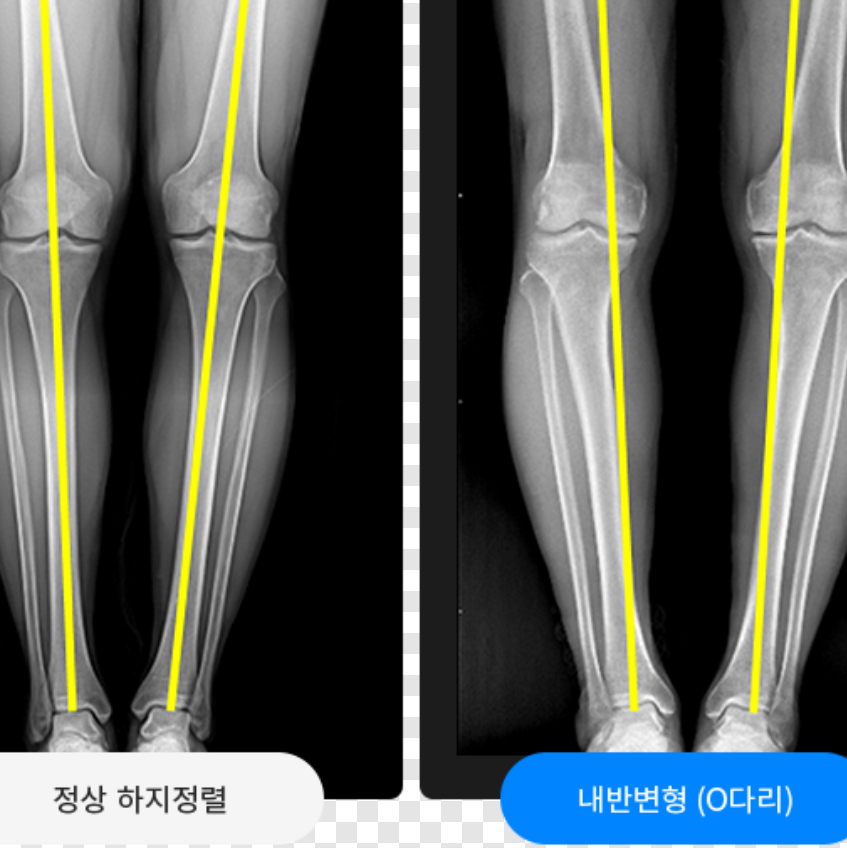

무릎과 무릎 사이가 벌어지는 내반슬(오자다리)은 영유아기에 많이 나타나지만 나이 들어 퇴행성으로도 생긴다.

무릎관절의 변형이 생겨 오다리가 되면 무릎 안쪽 연골에 더 많은(거의 모든) 하중이 걸린다. 관절의 부하를 줄이기 위해 심지어 체중을 감량하라는데, 무릎 관절 좌우 연골에 전체적으로 고르게 하중이 분포하지 않고, 안쪽 연골에만 하중이 집중되면 그 부분이 가속노화하게 된다. 연골의 수명이 다하면 결국 인공관절 수술 외에는 방도가 없다. 많은 정형외과 병원에서 오다리를 교정할 것을 권한다. 교정의 방법은 정도에 따라 운동, 장치(깔창 포함) 및 기구 등이 있지만, 종아리 뼈를 쐐기형으로 잘라 벌려 교정하는 수술(근위경골절골술)도 있다.

노화로 인한 오다리가 무릎연골을 빨리 노화시키니, 오다리를 빨리 교정하여 연골의 수명을 늘리라는 것이다.